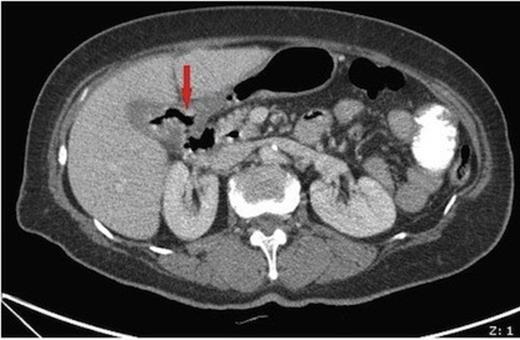

On examination the abdomen was mildly distended though soft, with active bowel sounds. Laboratory results were unremarkable. Plain abdominal radiograph showed pneumobilia. A subsequent CT abdomen (figure 1) showed a thick walled gallbladder with inflammatory changes and a fistula to the adjacent duodenum. Also demonstrated was a >2cm gallstone within the caecum, along with four smaller stones within the terminal ileum, and features of small bowel obstruction.

Axial CT image showing a thick walled gallbladder with inflammatory changes and a fistula to the adjacent duodenum